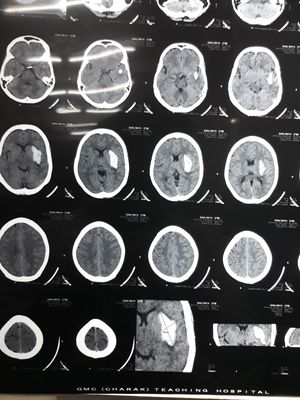

Significance of Siriraj scoring in Stroke? What might be the cause in this presentation?

Hemorrhagic stroke

Hemorrhagic stroke due to damage of middle cerebral artery territory

She's 55 yrs Female..It is one of the imp cause..bt not quite in this patient ! Pt is a known case of HTN ..she presnted with Hypertensive Urgency ! Arterial damge due to HTN